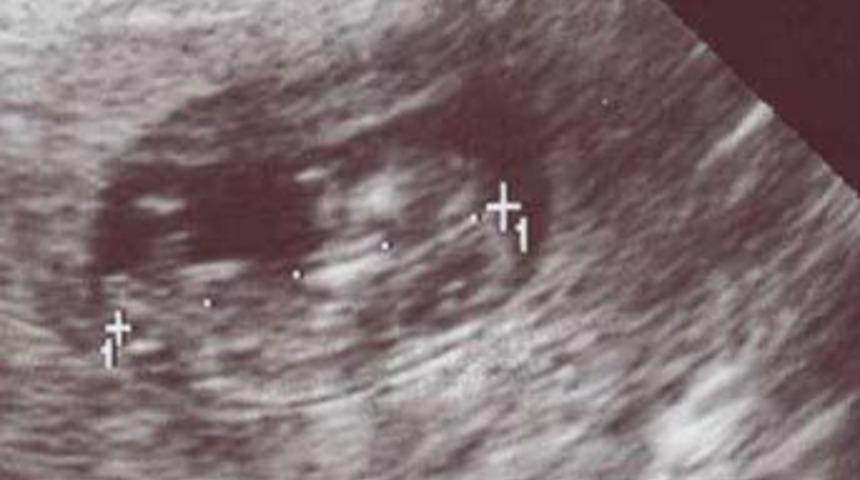

Bebeğin cinsiyetini öğrenmenin 40 yolu

Bebeğinizin cinsiyetini merak ediyorsanız genel durumunuzu gözden geçirerek kız mı yoksa erkek mi olacağını anlayabilirsiniz. Yüzlerce yıldır, bebek bekleyen anneler bebeklerinin cinsiyetini tahmin eden güvenilir metotlara bel bağlamışlardır.